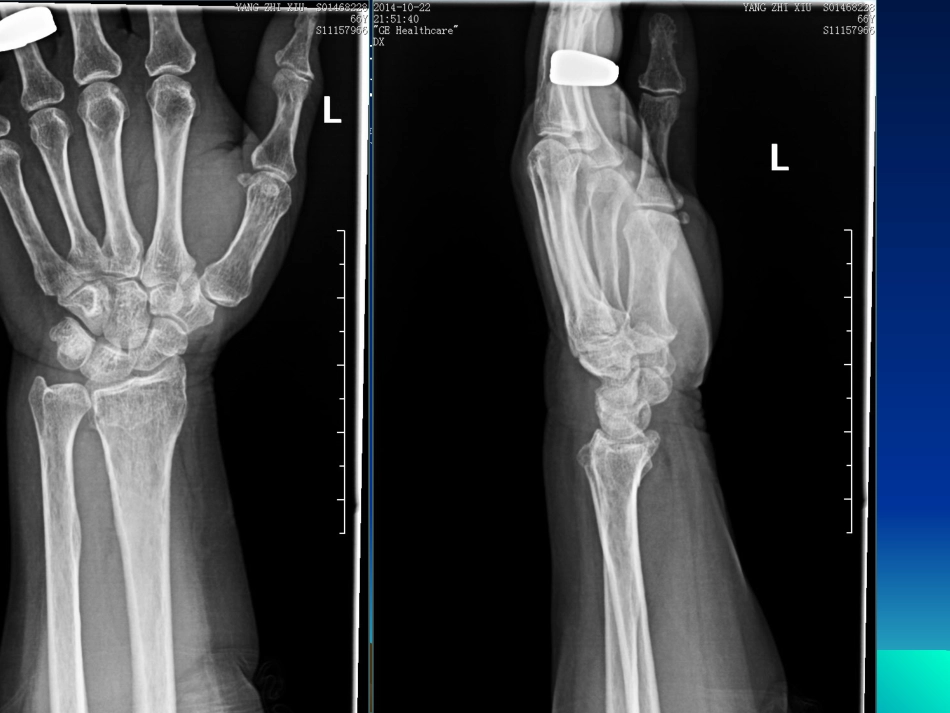

平片容易遗漏的骨折征象小结(一)鲁伦博14-10-26•一、腕关节正侧位1.女66岁外伤腕关节腕关节CTCT•2.男19Y外伤侧位重拍侧位重拍•44男男16Y16Y外伤外伤•5女55Y外伤6.6.女女1212岁外伤岁外伤7.7.男男3434岁外伤岁外伤桡骨远端骨折桡骨远端骨折•是指骨折发生在桡骨下端2-3cm范围内的骨松质部位。•主要为三种:a.colles’骨折。患者掌侧着地,常伴有远侧骨折断端向背侧倾斜,掌倾角减少或成负角。典型者伤手呈银叉畸形b.Smith骨折。又称反colles’骨折。患者手背着地,c.Barton骨折。腕关节半脱位伴随桡骨远端骨折。也即桡骨远端骨折累及桡腕关节面。腕关节正侧位阅片的时候应该注意的一些问题:正位片腕骨的情况:1.关节间隙宽度一致,成人约1-2mm2.相邻骨骼表面相互平行或一致。3.异常的关节间隙变窄可能是由于X线投照体位的原因,或者是退行性改变,很少是因为外伤所致。4.异常的关节间隙增宽可能是外伤所致。侧位片:1.桡骨远端背侧是光整的,没有褶皱,形态规则。2.桡骨远端、月骨和头状骨相互构成关节并位于一条直线上。(主要是应用于诊断月骨回旋性脱位和月骨周围性后脱位,前者时月骨凹空虚,桡骨和头状骨在一条线上,后者时桡骨和月骨保持在一条直线上,头状骨向后移位,和月骨不在一条直线上。)3.桡骨关节面有一向掌侧倾斜的角度,倾斜角平均为10°。桡骨远端骨折在复位后影像学上的允许范围是:掌倾角应该桡骨远端骨折在复位后影像学上的允许范围是:掌倾角应该大于零度,桡骨高大于大于零度,桡骨高大于44毫米。毫米。(正位(正位XX线片上的桡骨茎突上端和尺骨茎突上端分别做一条线片上的桡骨茎突上端和尺骨茎突上端分别做一条水平线,两线高度之差即为桡骨高,在水平线,两线高度之差即为桡骨高,在1111至至12mm12mm区间内区间内的为正常)的为正常)二腰椎正侧位1.女66Y外伤2.男36Y外伤CT复查左T12、右L13.男28Y外伤CTCT复查复查T9T94.男60Y外伤CT复查左T12、右L3腰椎正侧位腰椎正侧位•特别要注意每个椎体的高度和密度变化。若有,建议做CT排除骨折。•脊柱极易损伤的部位是胸腰椎交界处,该处是从活动度较小的胸椎过渡到活动度较大的腰椎,又是胸椎后突和腰椎前突的交汇点。脊柱损伤常见于T12-L1.而胸腰椎椎体压缩性骨折又占脊柱骨折的90%以上。•腰椎前后正位:椎弓根间距从L1到L5逐渐增宽。•腰椎侧位片:所有椎体高度相同;椎体后缘凹陷。